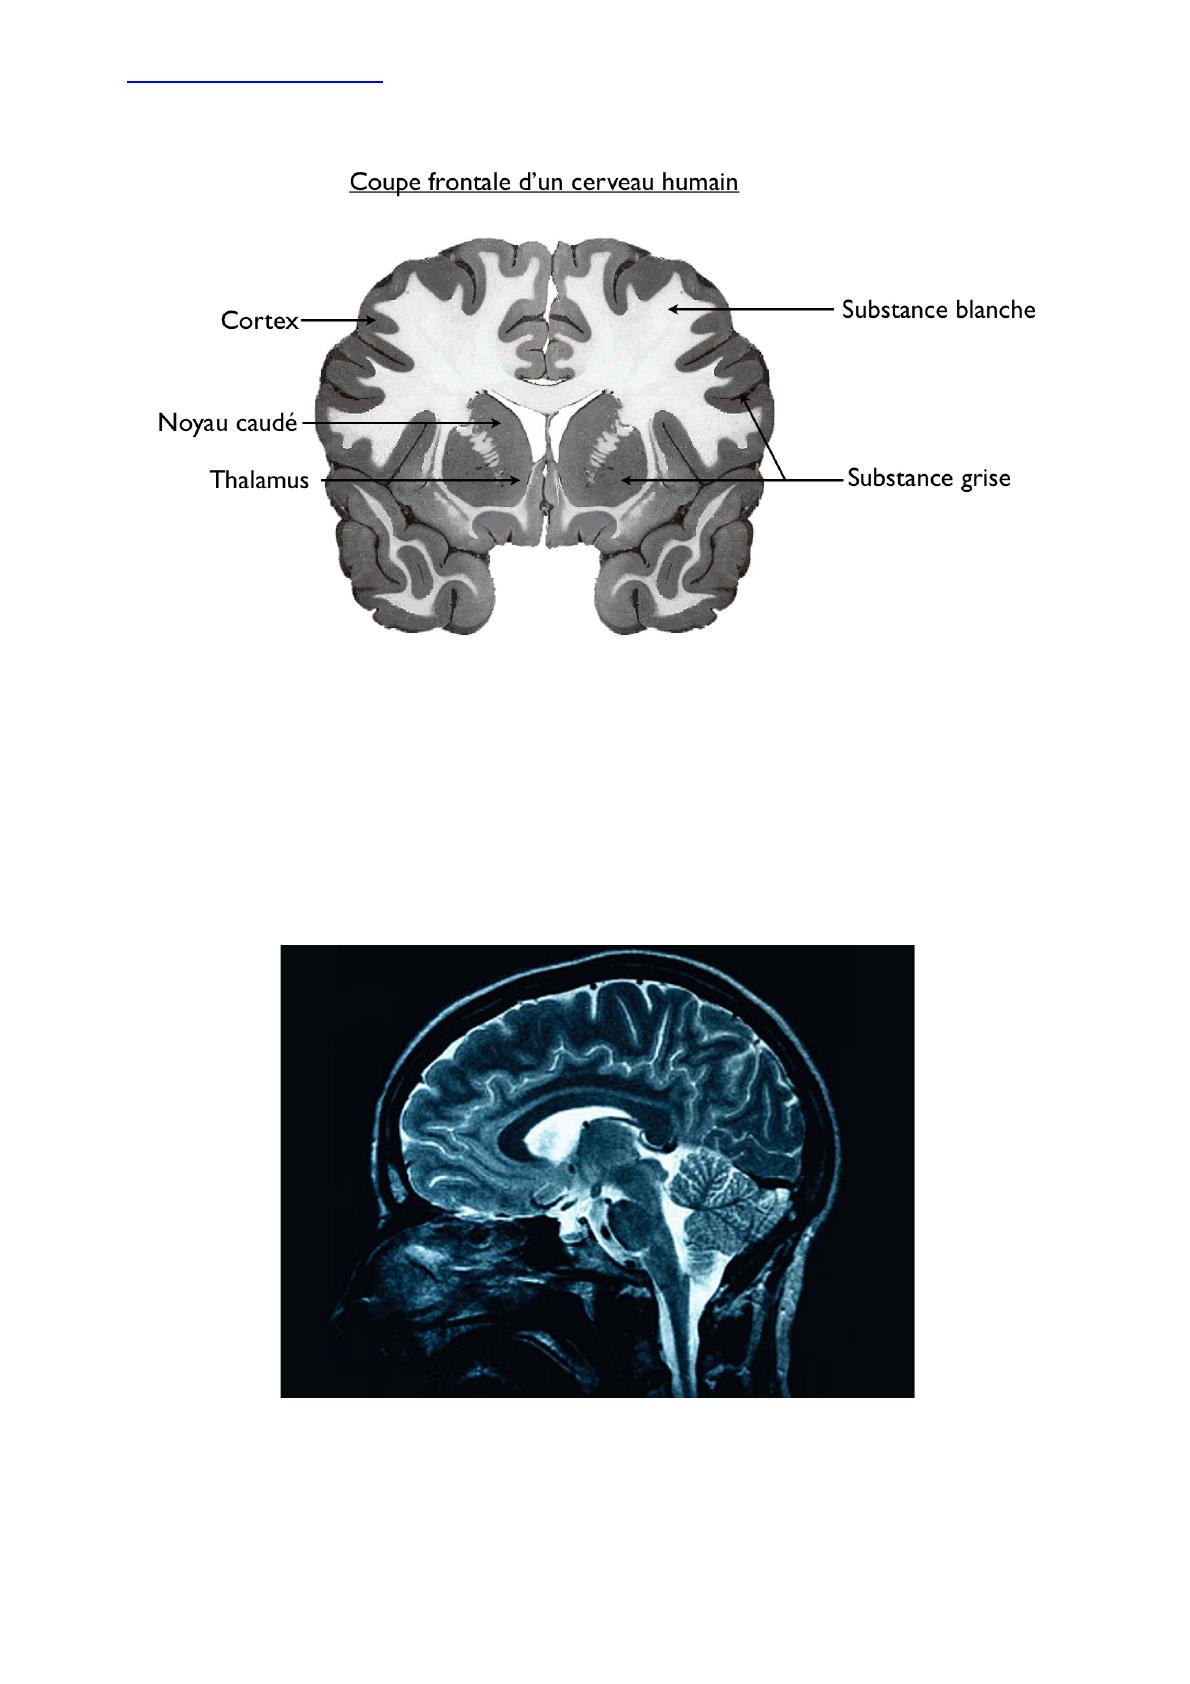

) 1,1,)Anatomie)du)cerveau)

Le!cortex!cérébral!est!la!partie!superficielle!du!cerveau!formée!par!la!substance!grise!

Le!cerveau!est!constitué!de!deux!hémisphères!volumineux,!présentant!de!nombreuses!circonvolutions,!

caractéristiques!de!l’espèce.!Ces!circonvolutions!ne!sont!pas!tout!à!fait!symétriques!de!part!et!d’autre!du!

sillon!inter!hémisphérique.!

Le!cortex!cérébral!constitue!le!revêtement!externe!des!hémisphères!cérébraux,!il!!a!2!à!4!mm!d’épaisseur!

et!occupe!une!surface!de!2200!m2.!

Des!ponts!de!substance!blanche!permettent!la!liaison!entre!les!deux!hémisphères!

L’encéphale!est!une!structure!protégée!par!la!boîte!crânienne!rigide!après!la!naissance!(2!ans)!

Le!liquide!céphalorachidien!qui!remplit!les!cavités!de!l’intérieur!de!l’encéphale!constitue!une!véritable!

suspension!hydraulique.!L’encéphale!flotte!dans!ce!liquide!et!perd!ainsi!97!%!de!son!poids.!

Le!tronc!cérébral!est!l’axe!reliant!les!hémisphères!cérébraux!et!la!moelle!épinière.!

Le!cervelet!est!en!partie!recouvert!par!le!cerveau!chez!l’homme.!